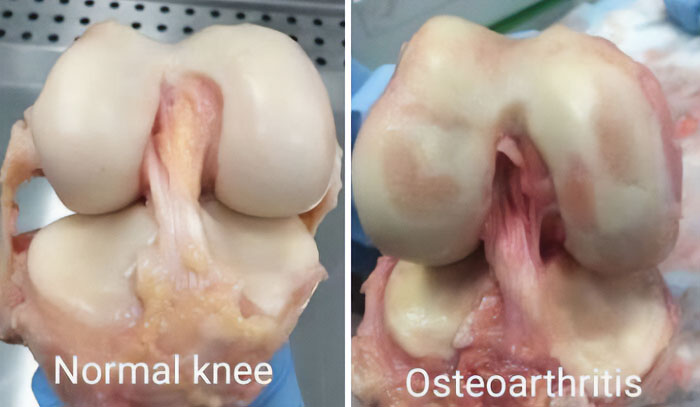

Normal Knee vs. Osteoarthritis

Thanks, I totally wanted to see what my knees will look like when I am old.